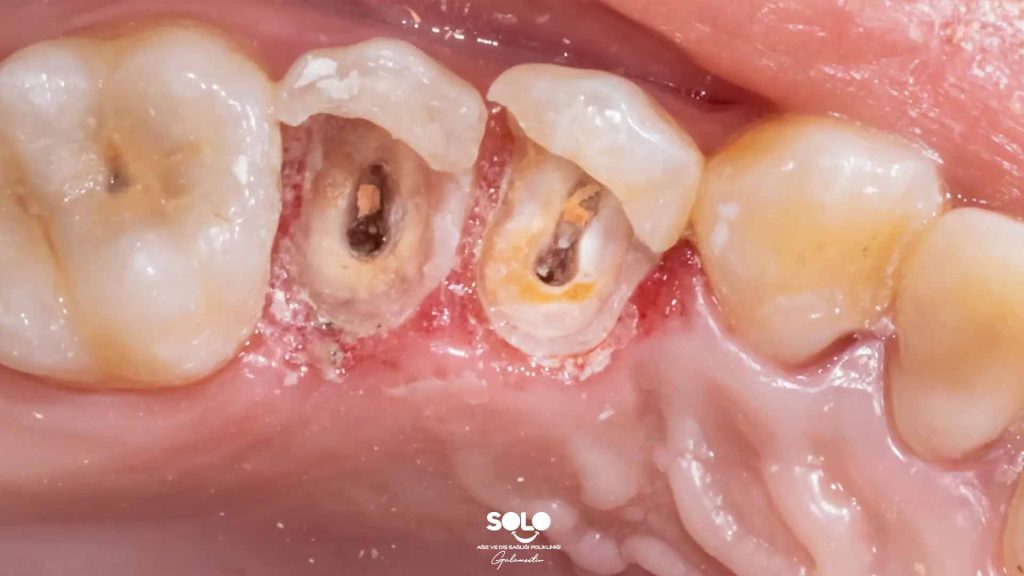

In the simplest terms, a dental lesion means a change in the tissue. In other words, it indicates that something in the structure of the tooth or the surrounding tissues is different from normal. This could be a small, visible cavity starting to form, wear or a crack in the enamel, or even a sign of infection developing at the tip of the tooth root. In short, a “lesion” is not a disease by itself; it is a finding that tells us something is not quite right.

Dental lesions are often caused by very “everyday” factors. Our teeth go through a real battle each day. The hot tea we drink in the morning, the coffee during the day, acidic beverages, sweet snacks… All of them leave small but meaningful effects on the tooth surface. If proper and regular cleaning is not added to the equation, plaque builds up and creates the perfect environment for bacteria. When bacteria combine with sugar, they produce acid, and this acid slowly weakens the enamel. What starts as a small white spot can gradually darken and turn into a cavity. In fact, the most common type of lesion is simply the early stage of tooth decay.

Sometimes the issue isn’t decay but trauma. A blow to the tooth, biting something very hard, or even small unnoticed accidents can create cracks on the tooth surface. Not every crack is clearly visible from the outside; in fact, a person may not notice anything for a long time. Yet microscopic damage may have already occurred inside the tooth. Similarly, gum problems can lead to inflammation around the root tip, which appears as a “lesion” on an X-ray. Especially in long-neglected cavities or cases requiring root canal treatment, the dark area seen at the root tip is actually the body’s response to infection.